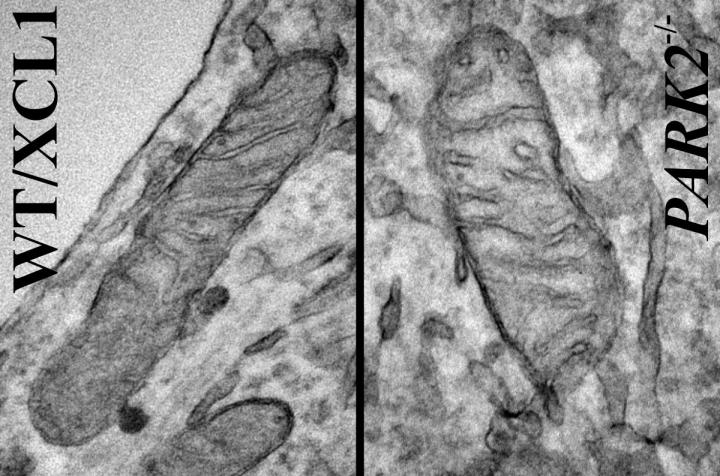

Mitochondria are energy-producing organelles found in large numbers in most cells and are necessary for life. Zeng says the Park2 mutation altered mitochondrial structure and function in dopamine producing neurons, causing them to die. Dopamine is an essential neurotransmitter which regulates movement and emotion.

The research involved making mutations in the Park2 gene in well-characterized induced pluripotent stem cell (iPSC) lines as well as generating iPSC lines from skin cells of four patients who have PD. "What we saw was extraordinary," said Zeng. "We saw the same characteristics in the dopaminergic neurons derived from patients as well as ones derived from the lines where the mutation was introduced."